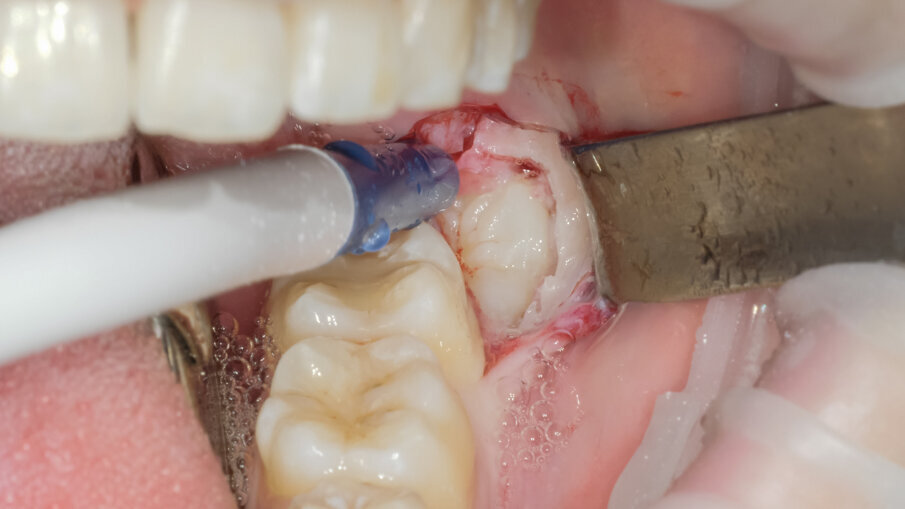

Si è presentata alla nostra osservazione la paziente A.M di 18 anni ASA 1 con disodontiasi di 38 e 48 lamentando fastidi localizzati all’area degli ottavi inferiori in fase finale di terapia ortodontica con allineatori trasparenti. Dall’ortopantomografia si poteva definire la classificazione di Pell e Gregory in classe II C e normoverso per quella di Winter (Fig 1). Vista la prossimità con il nervo alveolare inferiore, la incompleta formazione degli apici radicolari e la sintomatologia si è deciso insieme alla paziente di eseguire l’estrazione per ridurre i possibili rischi di danno neurologico dopo sottoscrizione del consenso informato. Previa anestesia tronculare della terza branca del V paio di sinistra con Carbocaina senza v.c. e plessica con Articaina 4% con v.c. 1:100000 si è proceduto all’incisione intrasulculare di 37 con scarico disto vestibolare. Lo scollamento del lembo mucoperiosteo è stato ottenuto mediante inserto PR1 al fine ottenere i vantaggi biologici come descritti da von See (Fig. 2).

L’ostectomia di accesso per evidenziare la corona è stata praticata mediante inserto SLO-H. Questo inserto nasce per il disegno della botola ossea nel rialzo di seno laterale, ma per la sua forma e il forte potere tagliente risulta molto efficace anche nella ostectomia peridentale (Figg. 3, 4). Mediante fresa a fessura in carburo di tungsteno montata su manipolo diritto sotto costante irrigazione di fisiologica sterile si è proceduto alla fase di odontotomia verticale in modo da separare la porzione corono radicolare mesiale da quella distale (Fig. 5).